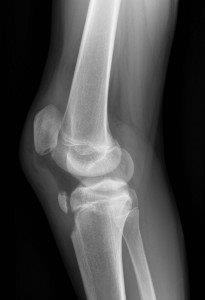

Avulsion of tibial tuberosity with superior displacement. Note high riding patella (above).